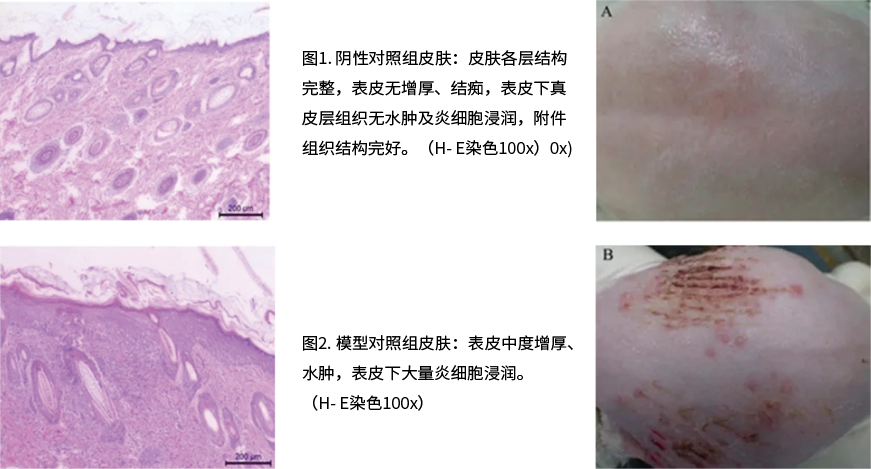

豚鼠皮肤单纯疱疹病毒(HSV-1)模型

豚鼠单纯疱疹性阴道炎(HSV-2)模型